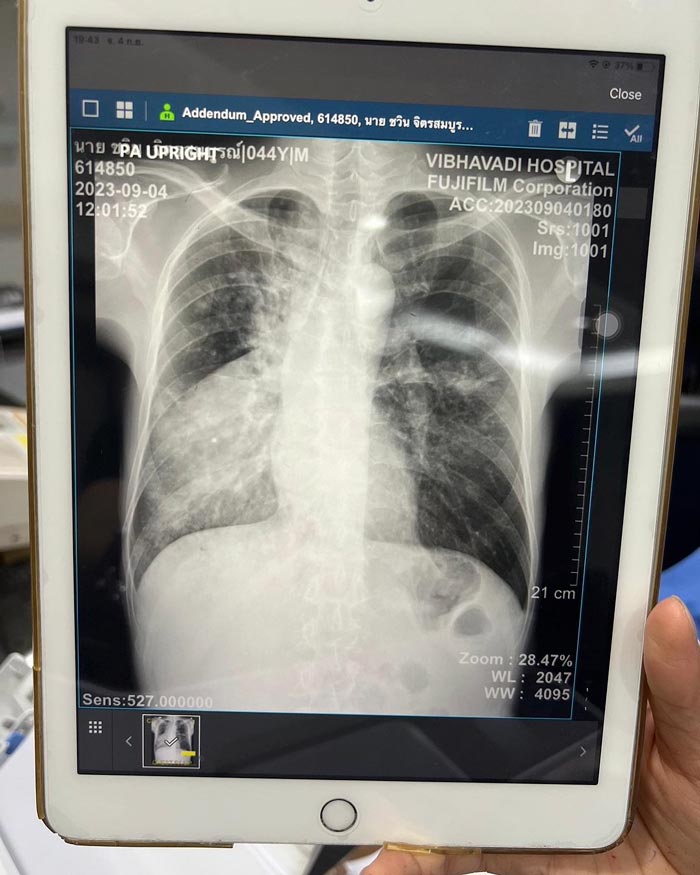

หลังจากที่มีข่าวว่า จั๊ก ชวิน นักร้องชื่อดังยุค 90 ป่วยเป็น วัณโรคปอด โดยรับเชื้อจากการคลุกคลีดูแลเพื่อนสนิทที่ป่วยวัณโรคและเพิ่งเสียชีวิตไปเมื่อต้นปีนี้นั้น ทำให้มีเพื่อนพ้องและแฟนเพลงมากมายส่งกำลังใจให้เจ้าตัวหายไว ๆ และกลับมาแข็งแรงในเร็ววัน

ล่าสุด (30 กันยายน 2566) จั๊ก ชวิน ก็ได้โพสต์ภาพอัปเดตอาการล่าสุด ระบุว่า ตอนนี้อาการค่อย ๆ ดีขึ้นตามลำดับ น้ำหนักหายไป 8 กิโลกรัม ทำให้ไม่ค่อยมีเรี่ยวแรง พยายายามจะกินเยอะ ๆ เพื่อเพิ่มน้ำหนัก และในสัปดาห์หน้าจะมีการนัดตรวจอีกครั้งว่าเชื้อหมดหรือยัง หากหมดแล้วก็จะสามารถออกนอกบ้านได้ พร้อมกับขอบคุณทุกคำอวยพรและกำลังใจจากทุกคนที่มอบให้เขาด้วย